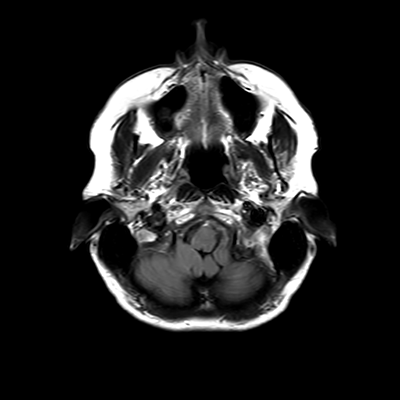

MRI brain (FLAIR)

2/18